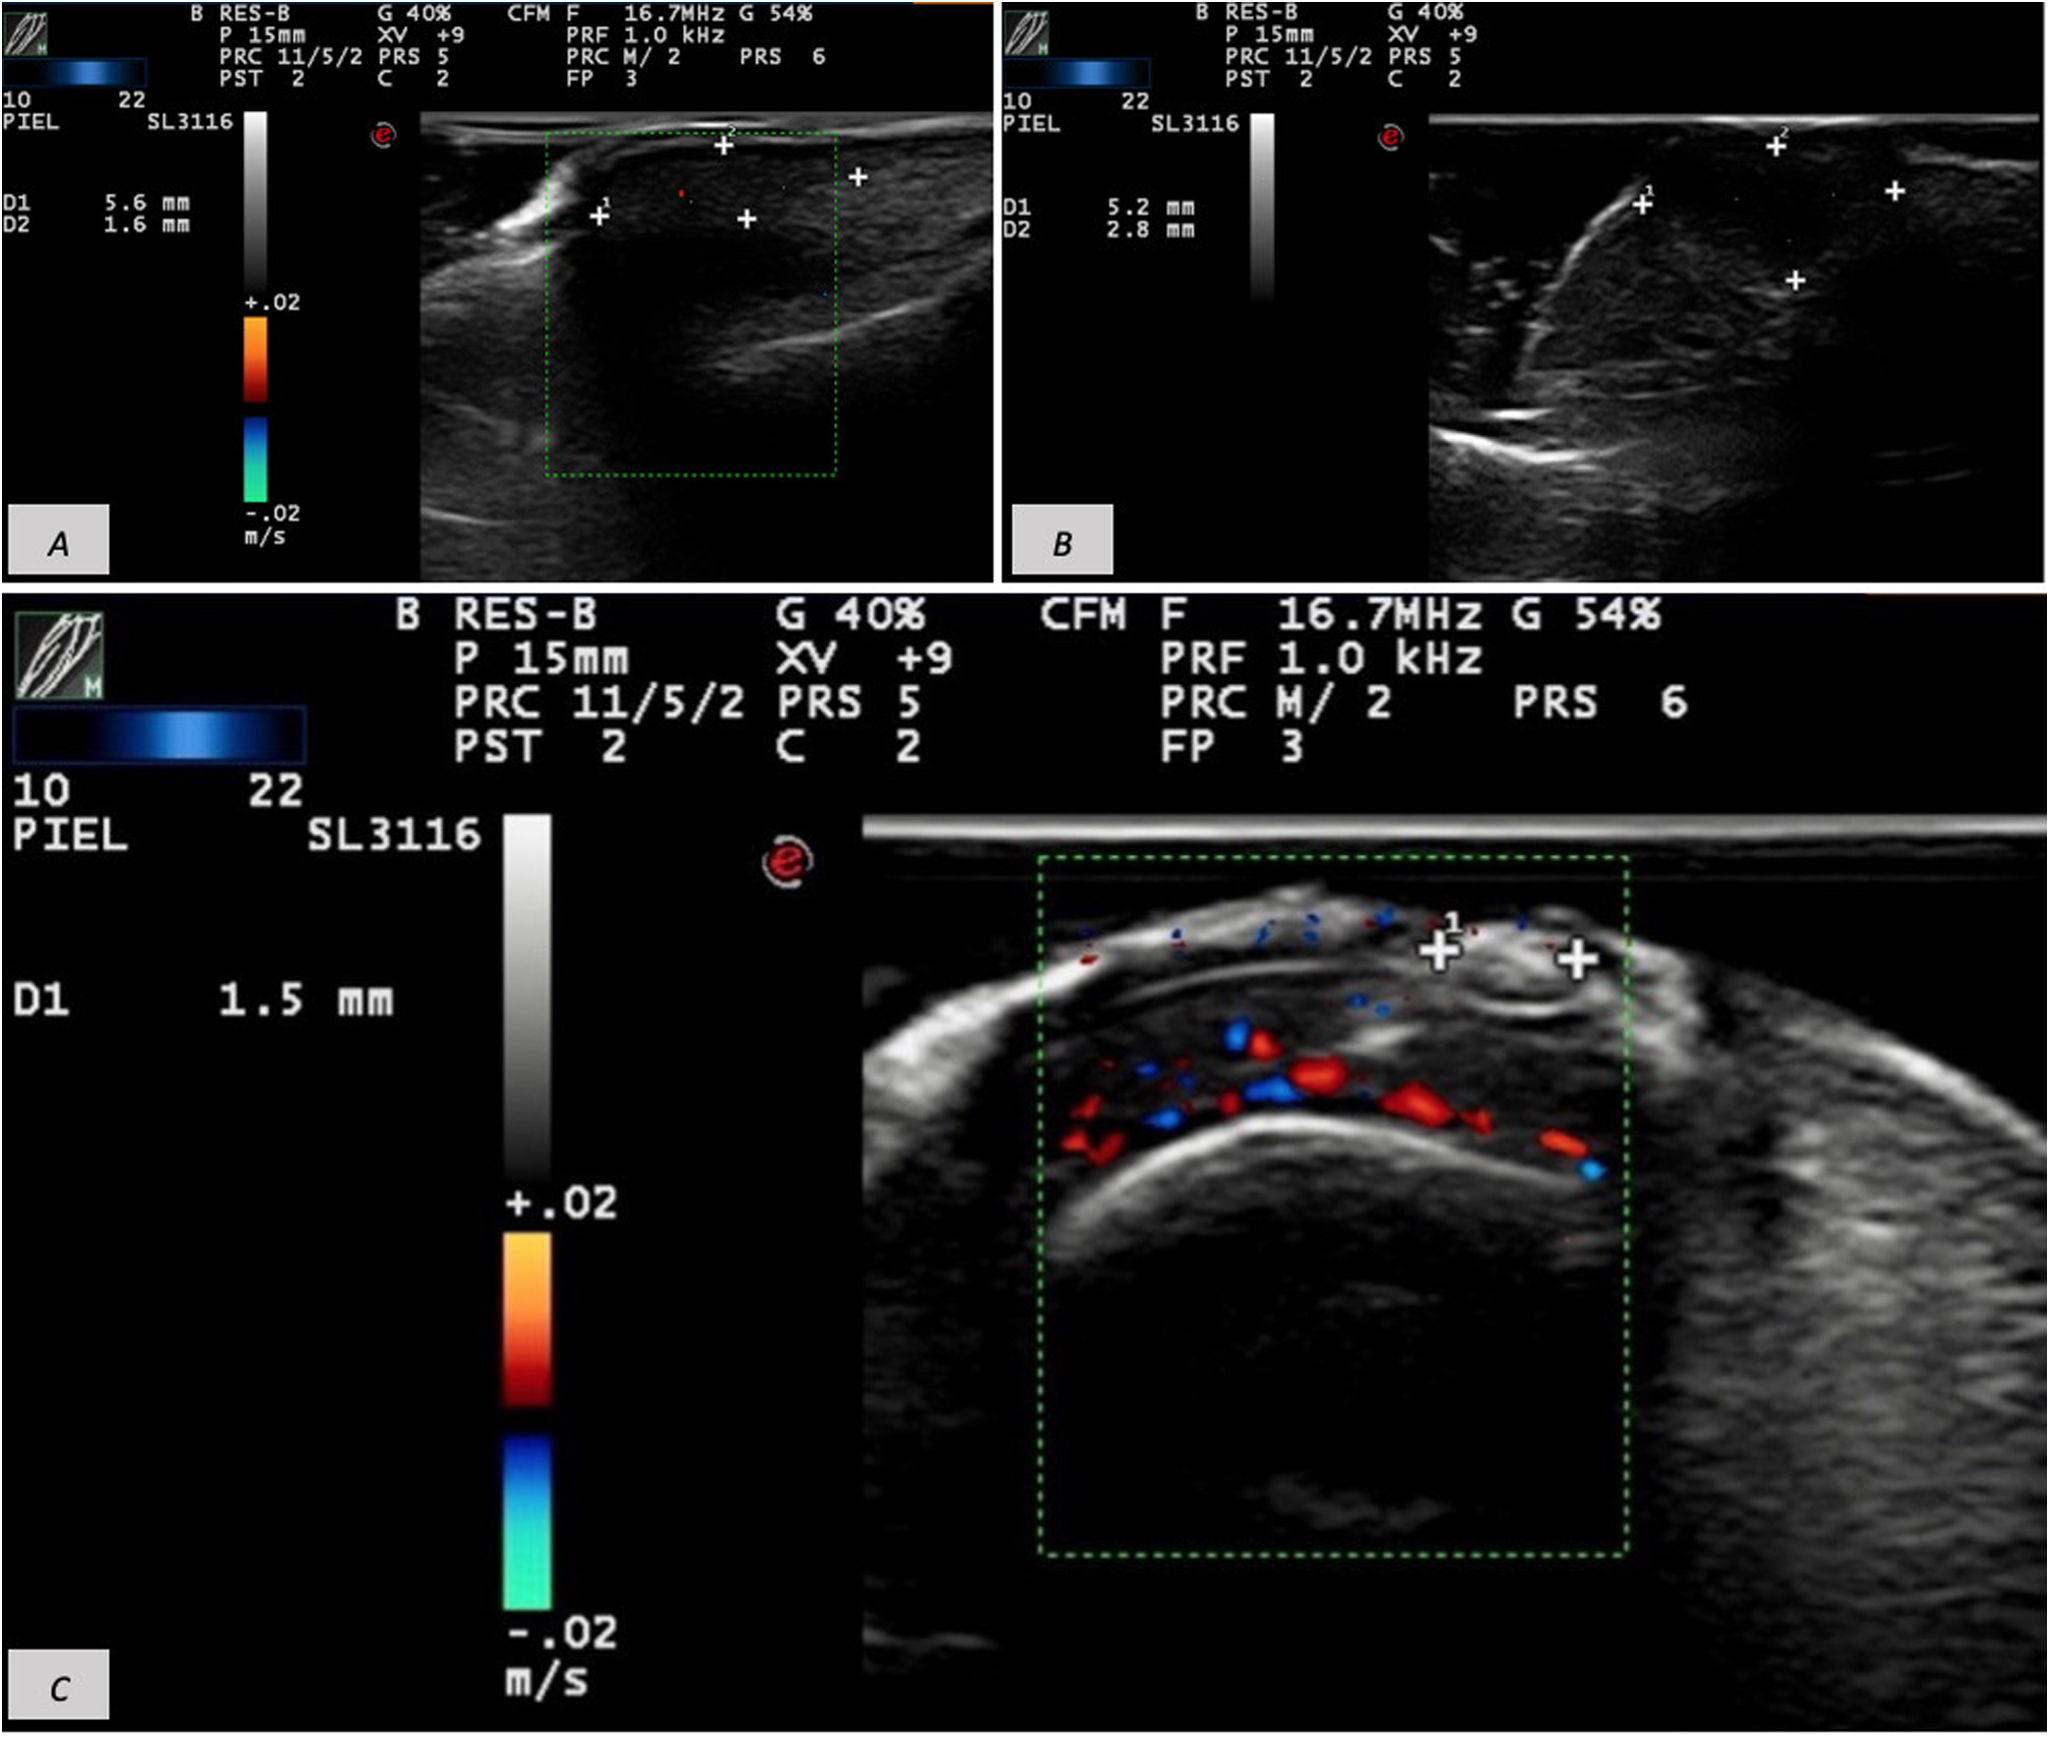

The 2nd patient was a 72-year-old woman presenting with a long-standing periungual nodule that was intermittently painful. She reported no changes in size or consistency and no drainage. Examination showed a well-defined, firm 5-mm subcutaneous nodule on the proximal nail fold of the 2nd finger of her right hand, with normal overlying skin. Ultrasound with an 18-MHz probe revealed the presence of a 5.6mm×1.6mm hypoechoic mass on the proximal nail fold, overlying the nail plate, without matrix involvement and minimal basal vascularity (Fig. 2A). With a presumptive diagnosis of acquired digital fibrokeratoma, excision was performed, and histology confirmed a periungual fibrokeratoma.

(A) Hypoechoic 5.6mm×1.6mm mass on the proximal nail fold overlying the nail plate without matrix involvement and minimal basal vascularity. (B) Well-defined 5.2mm×2.8mm hypoechoic lesion. (C) Frontal view of a 1.5-mm hyperechoic lesion, unrelated to underlying structures and without Doppler flow.

The 3rd patient was a 37-year-old woman who presented with a 2-year history of a stable, asymptomatic lesion on the 2nd toe of her left foot. Examination showed a 5-mm skin-colored, smooth-surfaced papule lateral to the nail of the 2nd toe, without inflammatory signs. Cutaneous ultrasound was performed with 18-MHz and 22-MHz probes. The 18-MHz probe demonstrated intact bone and nail plate. The 22-MHz probe revealed the presence of a 5.2mm×2.8mm well-defined hypoechoic lesion without Doppler flow (Fig. 2B). As in the previous cases, histopathology after excision confirmed an acquired digital fibrokeratoma.

Suspecting a subungual wart, dermatologic ultrasound was performed, demonstrating the presence of a 1.7mm×1.5mm soft tissue thickening beneath the proximal fold with no apparent relationship to underlying structures and no Doppler vascular flow (Fig. 2C). Wedge excision was performed, and histopathology revealed an ungual fibrokeratoma.